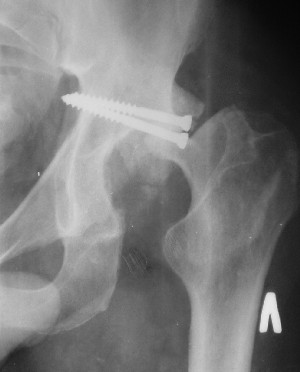

Послеоперационный снимок боковой 5/06/03

Больной 18 мая 2003 года в автоаварии получил перелом левой вертлужной впадины, вывих бедра. Госпитализирован в один из стационаров области.Вывих вправлен. В последствии бедро вывихивалось еще дважды. На консультацию был представлен снимок от 19.05.03г., больной переведен к нам 3.06.03г. Снимок при поступлении - перелом впадины, задне-верхний вывих бедра. 05.06.2003 г. выполнено открытое вправление вывиха левого бедра и остеосинтез стенки вертлужной впадины двумя винтами. Послеоперационный период без осложнений. Объем движений в левом тазобедренном суставе восстановился полностью. Выписан на амбулаторное лечение в удовлетворительном состоянии с рекомендациями 3 месяца ходить на костылях без нагрузки на оперированную конечность. На контрольных рентгенограммах левого тазобедренного сустава 13.10.2003 г. - признаки консолидации перелома; плотность, форма головки и состояние суставных поверхностей удовлетворительные. Разрешена дозированная осевая нагрузка, на конечность с использованием дополнительной опоры. 19.12.2003 г. больной обратился с жалобами на боли в левом тазобедренном суставе. На рентгенограммах левого тазобедренного сустава 19.12.2003 г., 20.02.04г. - асептичекий некроз головки бедра. 5.04.04г. - эндопротез. Сейчас ходит без трости, не хромает. Особенность эндопротезирования - при удалении винтов прослежена линия перелома заднего края впадины и предложено установить чашку несколько меньшего диаметра, чтобы она была покрыта несломанной частью.